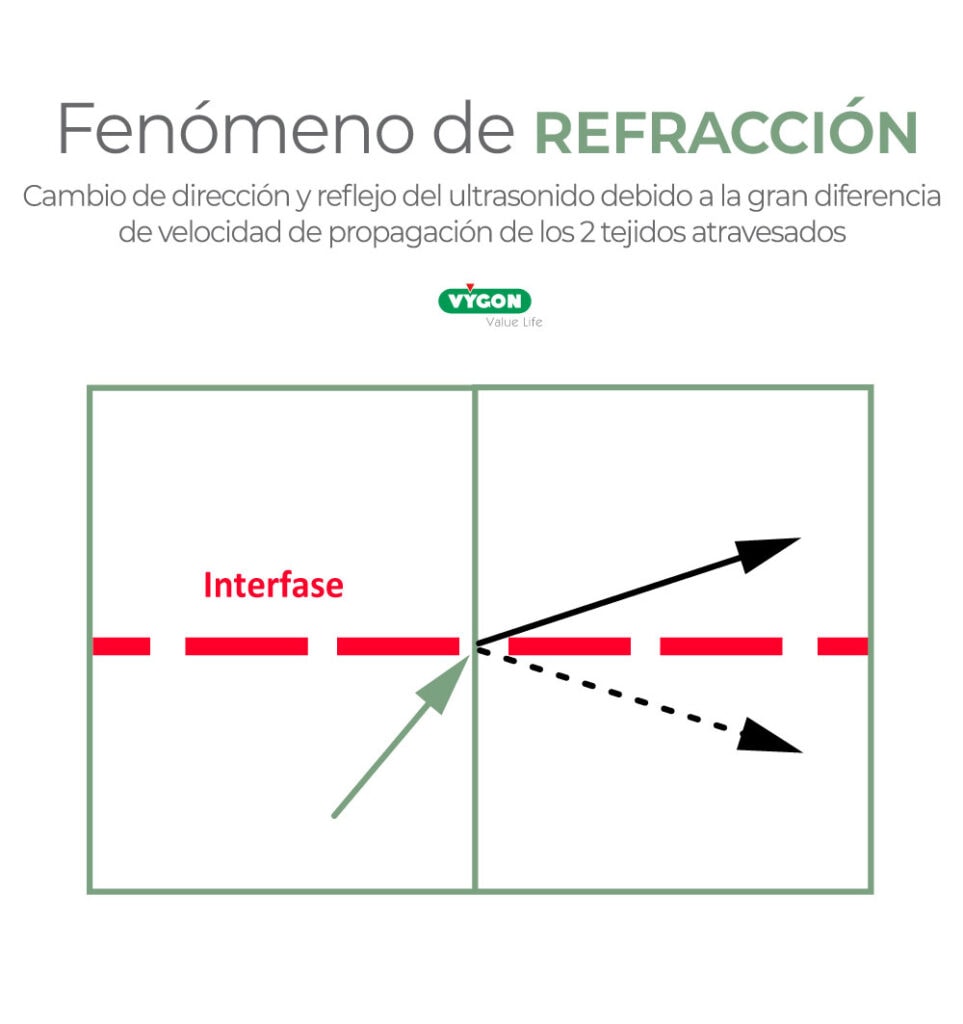

Refracción

Si el ultrasonido atraviesa dos medios con una gran diferencia en su velocidad de propagación (por ejemplo, aire y pleura), la onda cambiará de dirección y se producirá refracción. Además de ese cambio de dirección, se producirán reflejos de esa nueva dirección que se representarán en la pantalla en lugares diferentes de su origen.